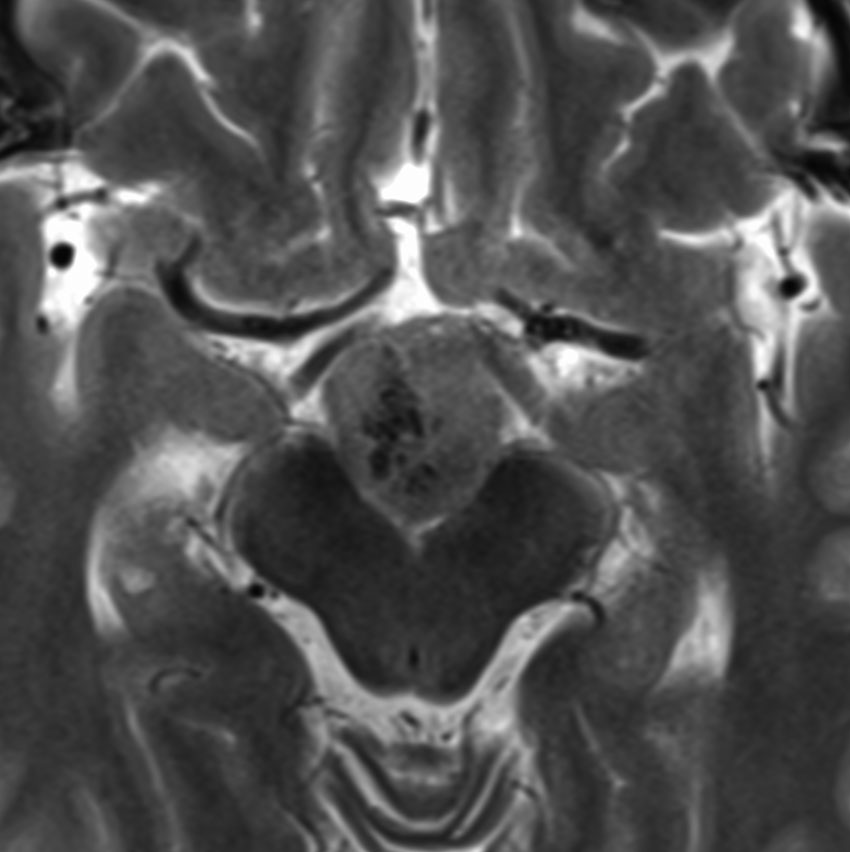

小脳毛様細胞性星細胞腫のFLAIR画像所見

壁在結節を伴うのう胞性小脳毛様細胞性星細胞腫は,結節を手術摘出すれば治癒するものです。しかし,あたかも腫瘍が残っているようなMRI画像所見が残ることがあります。

この例は,10歳の子どもに無症状で偶然発見された大きなのう胞性小脳毛様細胞性星細胞腫です。開頭手術で腫瘍結節は全摘出して腫瘍のう胞は縮小したままです。(画像はクリックすると拡大して見えます)

開頭手術で白く増強される結節部分だけを摘出しました。MIB-1はやや高値で3%と報告されました。病理組織診断は,WHO grade 1 毛様細胞性星細胞腫です。

6年後のMRI FLAIR画像です。摘出腔周囲の高信号域が残存しています。ここまで残ると腫瘍周辺浮腫ではありませんし,腫瘍細胞が左小脳半球に広範囲に浸潤して残存しているものだと判断されます。しかし,6年間で病変の増大傾向がありませんでした。この残存腫瘍(らしい所見)に対して放射線治療や化学療法を行うべきかどうか,結論は出ていません。しかし,経過観察を続けても増大して来ない例があることは確かです。一方で,この高信号領域が拡大したり,ガドリニウム増強される病変が再出現して治療がまた必用となることもあります。